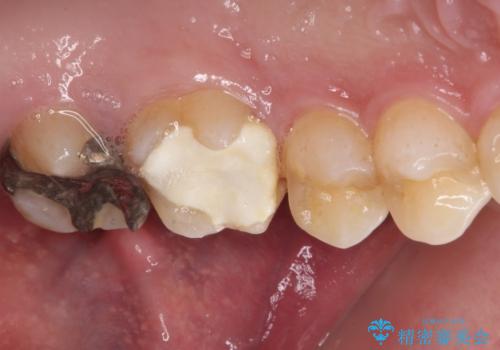

- 近医にて、銀歯の周りの歯が欠けてむし歯のようになっていると言われたとのことで来院された患者様です。

非常に咬合力が強く、銀歯やセラミックのような堅い素材では歯にダメージがかかり、治療を繰り返す可能性が高いと思われたので、ゴールドインレー(白金加金インレー、PGAインレー)にて、治療中の歯と銀歯が装着されている歯を修復治療することとしました。